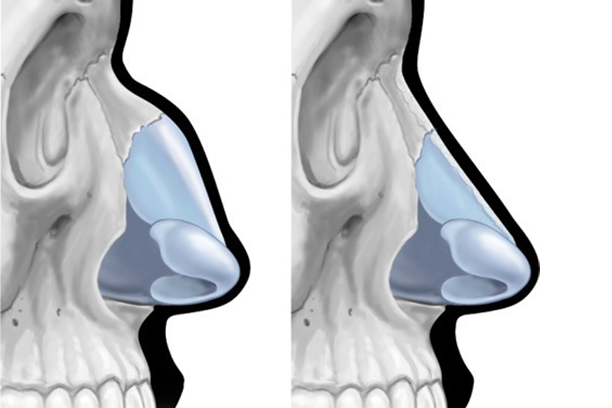

- Deviated Septum: Improves breathing by correcting a deviated septum.

- Facial Balance: Adjusts nose size to enhance facial symmetry.

- Blocked Nasal Passages: Opens obstructed nasal passages for easier breathing.

Enhances Facial Aesthetics – Reshapes the nose to create better symmetry and balance with other facial features.

Corrects Structural Issues – Fixes problems like a deviated septum, reducing nasal blockages and improving airflow.

Improves Breathing – Addresses internal obstructions such as enlarged turbinates for easier breathing.

Customizable Procedure – Can focus on tip refinement, bridge correction, nostril reshaping, or overall nose size reduction/enlargement.